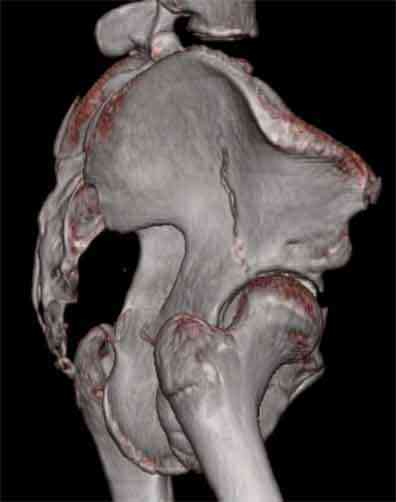

Не смог разглядеть на представленных картинках частичное повреждение левого КП, повреждение Денис1-2 справа? 3Д реконструкции в инлет и боковой проекциях убедительно не демонстрируют типа повреждения задних отделов тазового кольца(справа боковая масса скомпремирована), Наверное, у тебя есть возможность оценить тип перелома крестца по прямой проекции 3Д.

Насколько я понял из твоего письма, обращенного к анонимному vit, ты не видишь показаний к реконструкции перелома. Я бы взялся за реконструкцию(илео-ингвинальный доступ), хоть прошел и месяц после травмы: боковая 3Д показывает смещение нагрузочной зоны впадины, что однозначно будет способствовать разрушению хряща головки и впадины( особенно у 16 летнего пациента с ожидаемым высоким уровнем активности) + изменение геометрии впадины за счет неустраненного смещения фрагментов колонны (КТ, 3Д данные).

На мой взгляд, без реконструкции этот сустав обречен (концепция вторичной конгруэтности в данных условиях работать не будет), реконструкция дает шанс на восстановление функции сустава.

Сравнивая боковые проекции 3Д реконструкций, разница переломов очевидна: в предыдущем случае на боковой проекции не видно было ступени нагрузочной зоны суставной поверхности - это и объясняет приличную функцию сустава.

На 3D по линии перелома ацетабулум возможно сверху в подздошной кости уже есть сращение? или состояние перелома у молодых, после неполного (при пластической деформации) перелома.

По представленным материалам, мне кажется, перелом был передней колонны ацетабулум с минимальным вовлечением нагрузочной поверхности сустава, левосторенний повреждение КПС и лонных костей.

При свежем случае показана фиксация передней колонны к задней (снимки), компрессирующим винтом минимальным перкутанным методом по супраацетабулярной линии и в зависимости от состояния КПС.